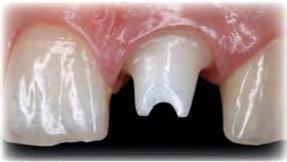

El innovador Disilicato de Litio (LS2) del sistema de cerámica vítrea IPS e.max CAD no solo ofece una altísima estética sino que también es de 2,5 a 3 veces más resistente 360 MPa que el resto de cerámicas de vidrio. Por ello, este material cubre todos los requerimientos estéticos y también representa una alternativa eficiente a las restauraciones unitarias de Zr02 (Zirconio).

El innovador Disilicato de Litio (LS2) del sistema de cerámica vítrea IPS e.max CAD no solo ofrece una altísima estética sino que también es de 2,5 a 3 veces más resistente 360 MPa que el resto de cerámicas de vidrio. Por ello, este material cubre todos los requerimientos estéticos y también representa una alternativa eficiente a las restauraciones unitarias de ZrO2. (Zirconio)

IPS e.max está avalado por la experiencia clínica que ha demostrado durante años, tanto en estética como en resistencia. La amplitud de elección del material, según el caso, en conjunción con la técnica empleada en nuestro laboratorio dotarán a los trabajos de la mayor estética para sus pacientes.